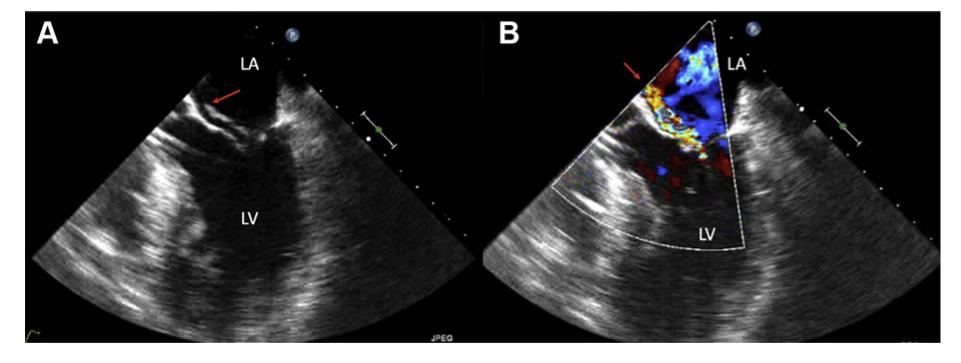

【诊断】超声诊断心梗后室间隔穿孔